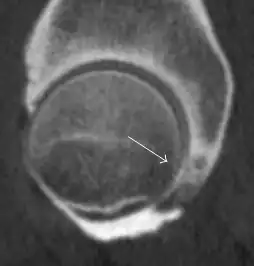

Most of the angles and measurements described in the plain radiograph section can be accurately reproduced on MRI. In addition, the superiority of MRI resolution with intra-articular contrast allows detection of labral and chondral abnormalities that may influence the choice of medical, percutaneous, or surgical management (Figure 9).[1]

Figure 9:

MR arthrography has proven superior in accuracy when compared to native MR imaging. It is considered the best technique to assess the labrum. Knowledge of the normal variable morphology of the labrum helps to differentiate tears from normal variants. A triangular shape is most commonly seen in 66% of asymptomatic volunteers, but round, flattened, and absent labra can also be found in asymptomatic populations. MR arthrography has demonstrated sensitivity over 90% and specificity close to 100% in detecting labral tears. Loose bodies are demonstrated as filling defects surrounded by the hyperintense gadolinium.[1]

Association between labral tears and chondral damage has been demonstrated. This underscores the interaction between cartilage and labrum damage in the progression of osteoarthritis. Chondral damage to the posteroinferior part of the acetabulum as a contrecoup lesion occurs in approximately one-third of pincer cases secondary to persistent abutment on the anterior part of the joint leading to a slight posteroinferior subluxation. This is considered a bad prognosis sign.[1]

MR arthrography can also demonstrate ligamentum teres rupture or capsular laxity, which are debated causes of microinstability of the hip. Elongation of the capsule or injury to the iliofemoral ligament or labrum may be secondary to microtrauma in athletes. MR can demonstrate abnormalities in these cases, such as increased joint volume or a ligamentum teres tear (Figure 9).[1]